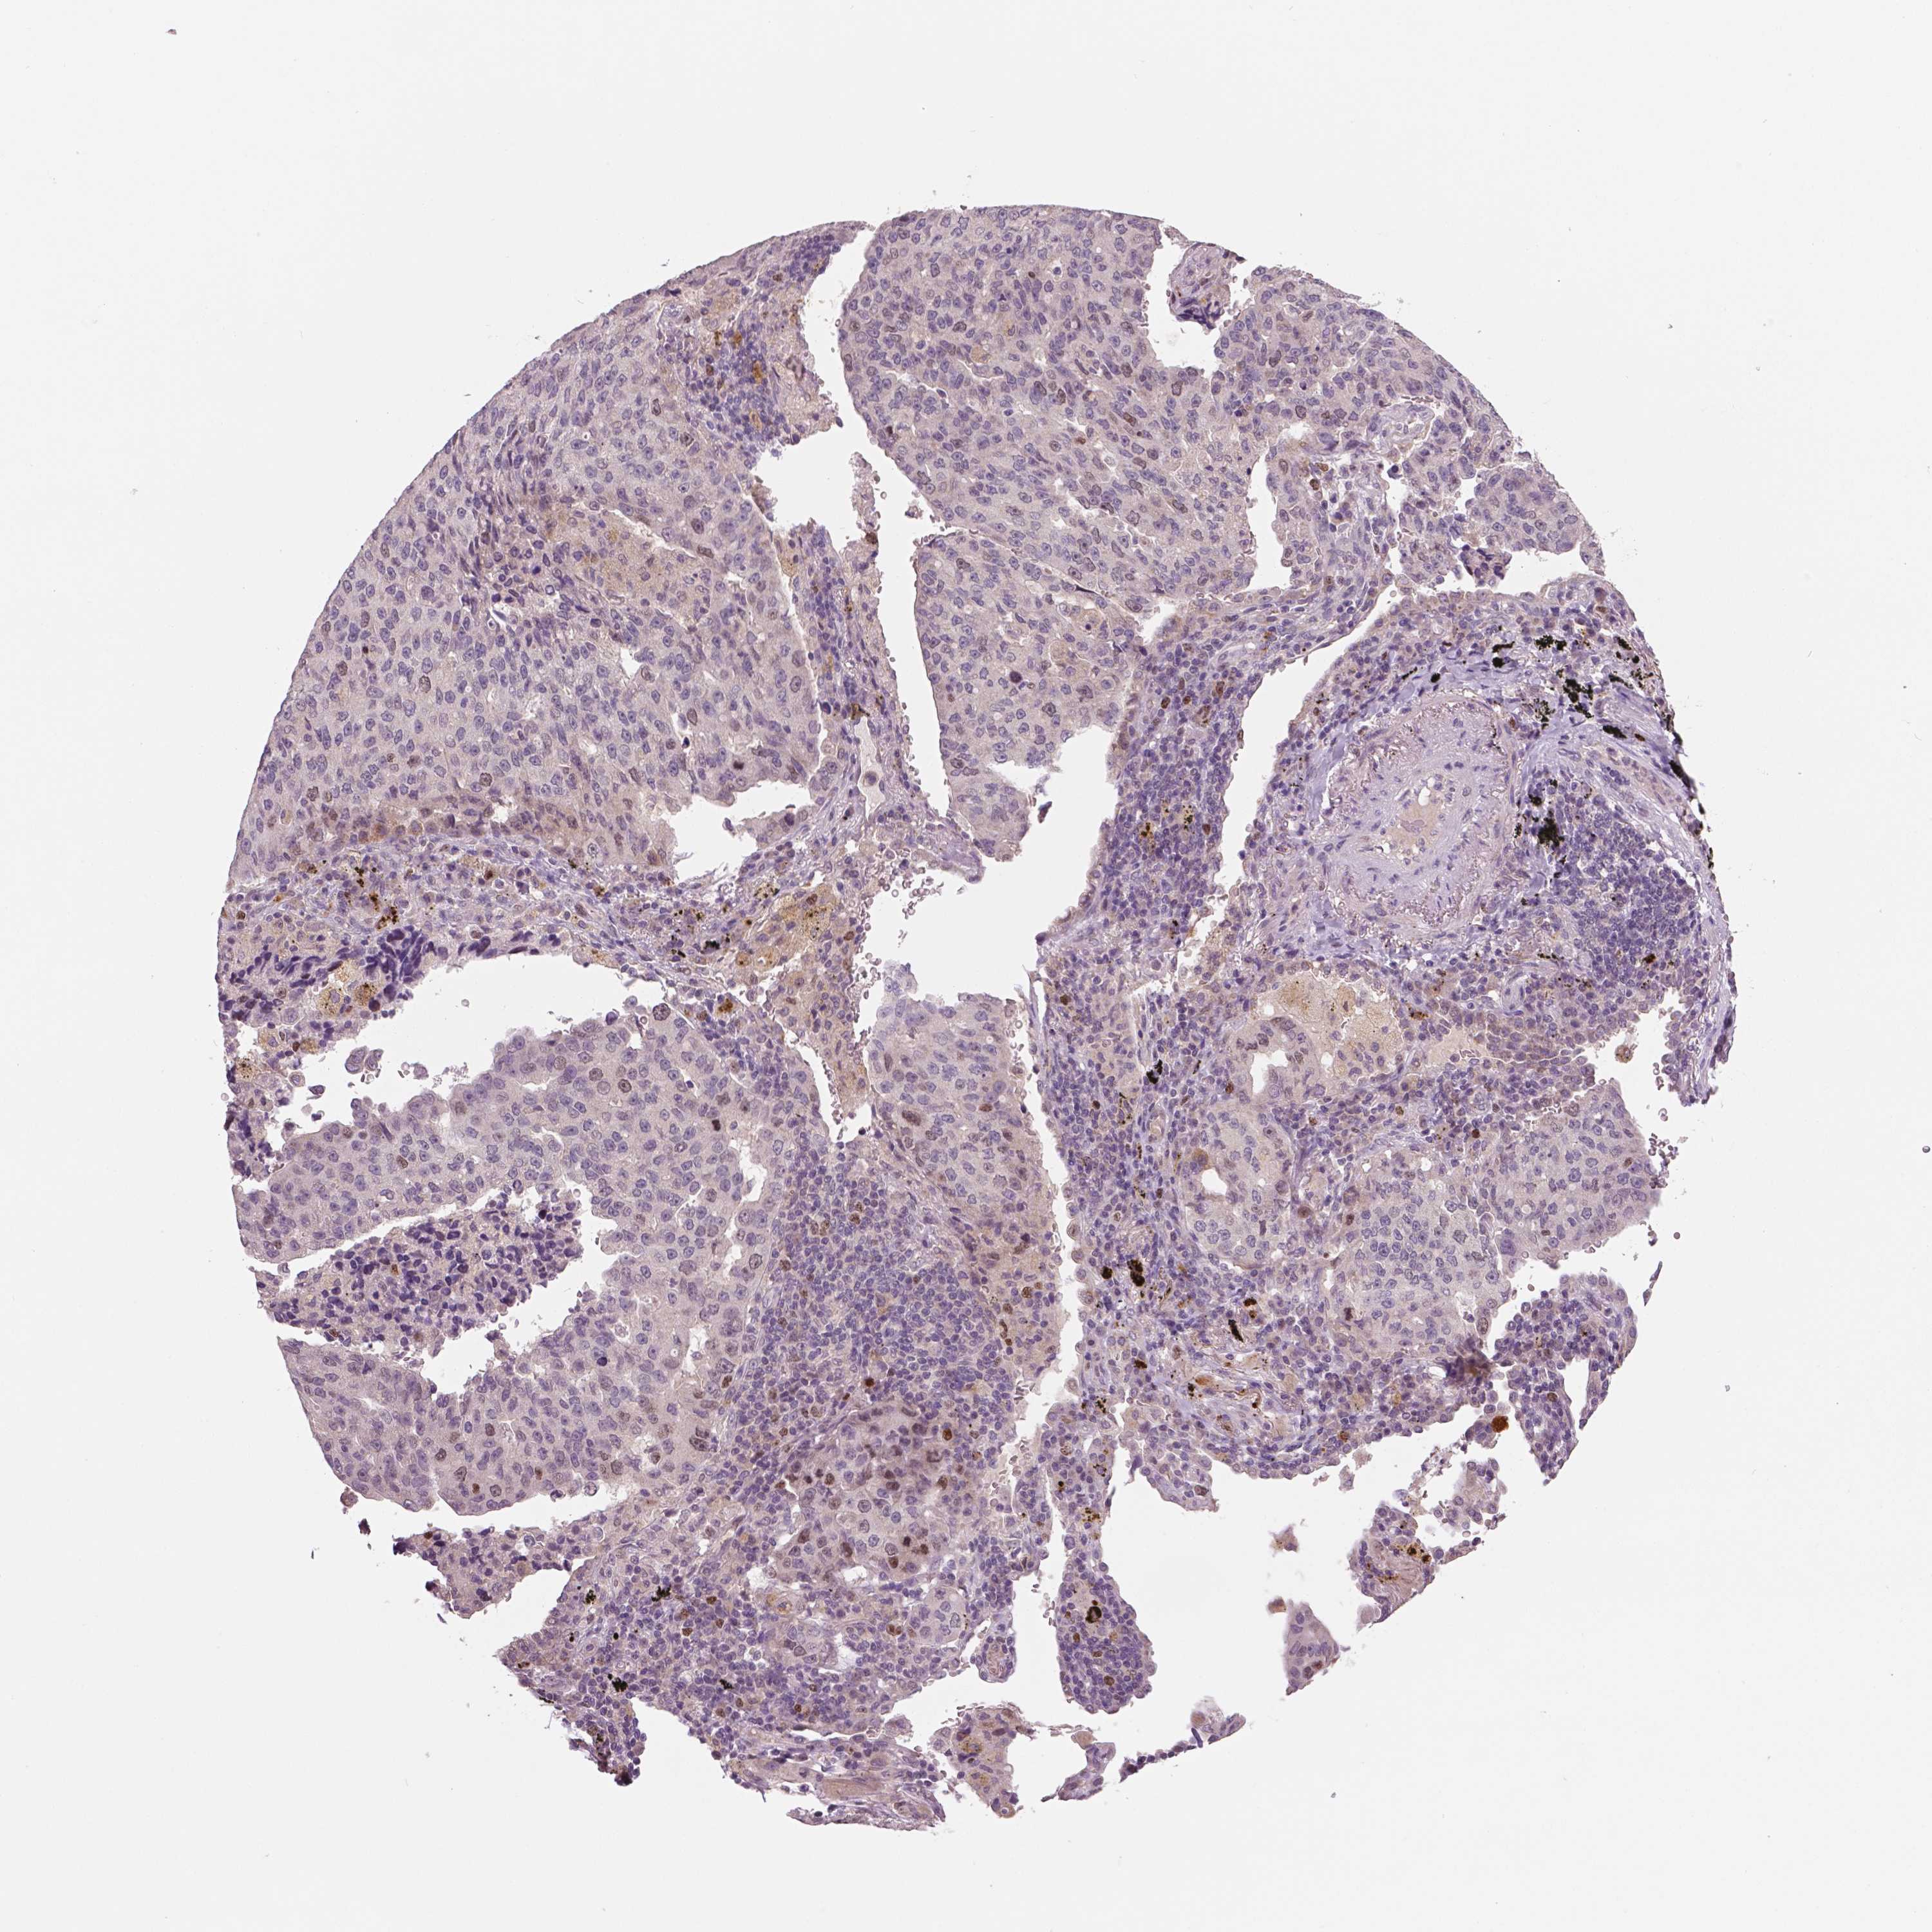

MKI67 is not prognostic in Lung Squamous Cell Carcinoma (TCGA)

: 13.48

Average pTPM 15.6

Number of samples 489